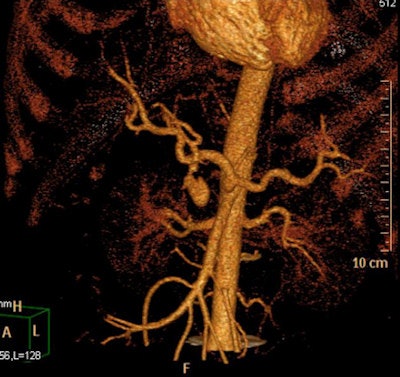

Left: CT performed after laparotomy. Retroperitoneal hematoma in the upper abdomen surrounds the abdominal aorta also involves left perirenal space with thickening of pararenal fascia. A 3.5 mm outpouching from the left lateral wall of the upper abdominal aorta just inferior to the level of the coeliac axis (L1 level) is located short distance anterior to a tiny arterial branch. This is the epicenter of the upper abdominal hematoma and may represent small false aneurysm either from traumatic transection or at the site of avulsion of a small aortic branch. No intimal dissection flap is identified. A large volume pneumoperitoneum is also present. Right image: Repeat CT angiography a week later demonstrated spontaneous thrombosis of the tiny false aneurysm. Image courtesy of Dr. Andrew Lawson and radiopaedia.org. radiopaedia.org/cases/traumatic-abdominal-aortic-false-aneurysm."They can involve any arterial segment or even a cardiac chamber. Examples include femoral artery pseudoaneurysm (relatively common site due to femoral punctures), carotid artery pseudoaneurysm, visceral arterial pseudoaneurysm, peripheral arterial (limb) pseudoaneurysm, left ventricular pseudoaneurysm, and brachiocephalic artery pseudoaneurysm," wrote Weerakkody and D'Souza. "Some of the imaging features may be dependent on location. Due to the turbulent forward and backward flow, a characteristic yin-yang sign may be seen on color flow, while a 'to and fro' pattern may be seen with pulsed Doppler."